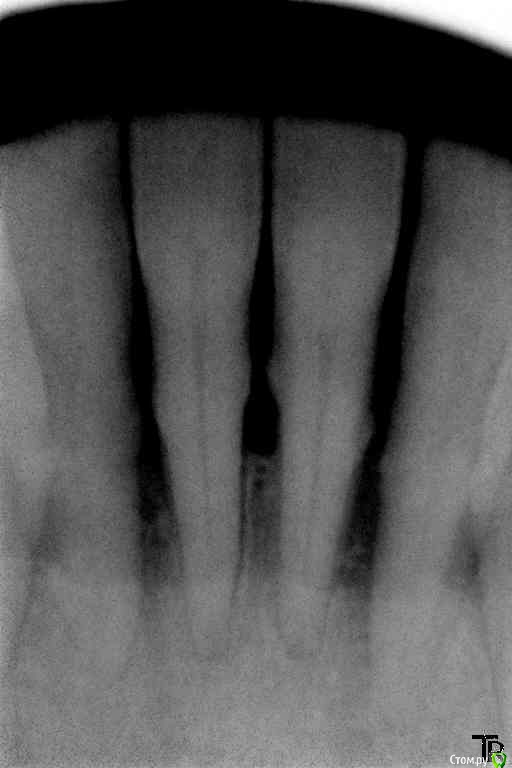

Витторио Орлионе Опубликовано 14 февраля, 2016 Поделиться Опубликовано 14 февраля, 2016 12.02.2016 Обратился Мужчина 72 года рождения с жалобами на боли и припухлость в области фронта нижней челюсти, на зубах налёт от стоматотофита, рецессия десны и резорбция кости,подижность 2 степени у зубов 4.2, 4.1 и 3 степени у зубов 3.1 и 3.2 десна вздулась в области зуба 3.2. Перкуссия да и просто прикосновения вызывали жуткие боли. Вколов 2 карпулы ультракаин дс форте инфильтративно + лидокаин, так и не обезболились, хотя губа занемела. Промыл хлоргексидином и оставил смесь из метрогила и трихопола под дессной, пациент при этом от боли вжимался в кресло. А как встал, ноющие боли прошли, а до зубов по прежнему не дотронуться. До посещения начал пить аугментин. Был 2й день приёма. Пришёл 14.02. Не болит, припухлость спала. 2 карпулы ультракаина дс форте не обезболилил. манипуляции повторил. Отправил до наступления реммиссии. Снимки прилагаются. Вопросы:Как обезбаливать в таких случаях?Удалять ли 3.2?Обязателен ли открытый кюретаж?Да и вообще как бы вы его вели? Ссылка на комментарий

Витторио Орлионе Опубликовано 21 февраля, 2016 Автор Поделиться Опубликовано 21 февраля, 2016 Развязка: Ментальная анестезия с двух сторон, ультразвуковая чистка зубов 3.3-4.3, промывание 0.05% хлоргексидин, оставлен метрогил+доксициклин. Пациент допивает аугментин. Боль в области зуба 3.2 сохранилась только при надавливании, в покое не беспокоит. Было рекомендовано его удаление. Ссылка на комментарий